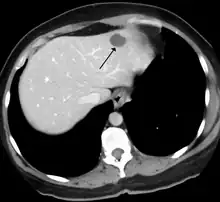

Tumor hepático ou tumor do fígado é qualquer crescimento anormal dentro da estrutura do fígado, incluindo neoplasias benignas e malignas, originado no órgão (primário) ou fora dele (metástase), infecciosas ou não.

Os tumores hepáticos benignos são relativamente comuns e geralmente não causam sintomas. A maioria dos tumores benignos é detectada apenas quando um exame de imagem, como ultrassonografia, tomografia computadorizada (TC) ou ressonância magnética (RM), é feito por uma razão não relacionada com o tumor. Raramente, esses tumores causam desconforto na parte superior direita do abdômen, fazem com que o fígado aumente (hepatomegalia) ou causam sangramento na cavidade abdominal. [1]

A maioria dos cânceres de fígado são metástases de outros tumores, geralmente de origem abdominal como o câncer de cólon, câncer de ovário e câncer renal, mas também são comuns os originados de um câncer de mama e câncer de pulmão.

O câncer hepático primário mais frequente é o carcinoma hepatocelular (também denominado hepatocarcinoma). A principal causa de carcinoma hepático é cirrose devido a hepatite B, hepatite C ou alcoolismo. Também pode ser causado por aflatoxinas produzidas por fungos que contaminam alimentos. Obesidade, diabetes e tabagismo são importantes fatores de risco. [4]